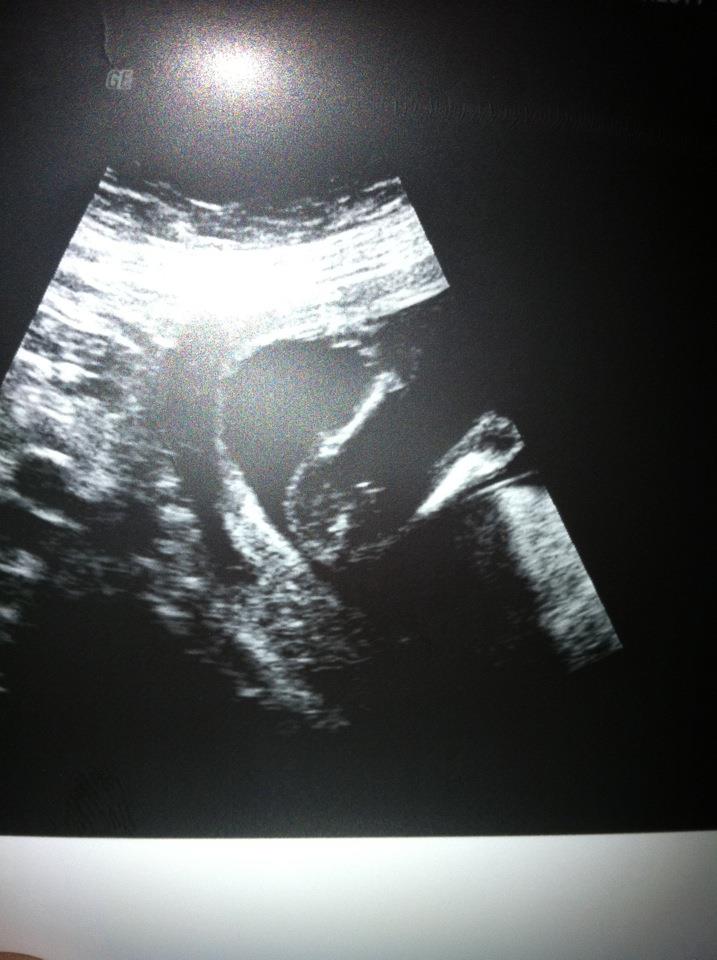

Had my gender scan yesterday, when i first saw i was sure boy until she said she couldnt see mushroom asbaby was moving loads so thought girl, however two lines although their sticking out different to all the potty shots of girls iv seen, she didnt seem to sure and tbh all my symptoms areboy ive got 3 daughters and a son. got my 20 wk scan in 4 weeks so just wondered what you all thought?boy or girl x